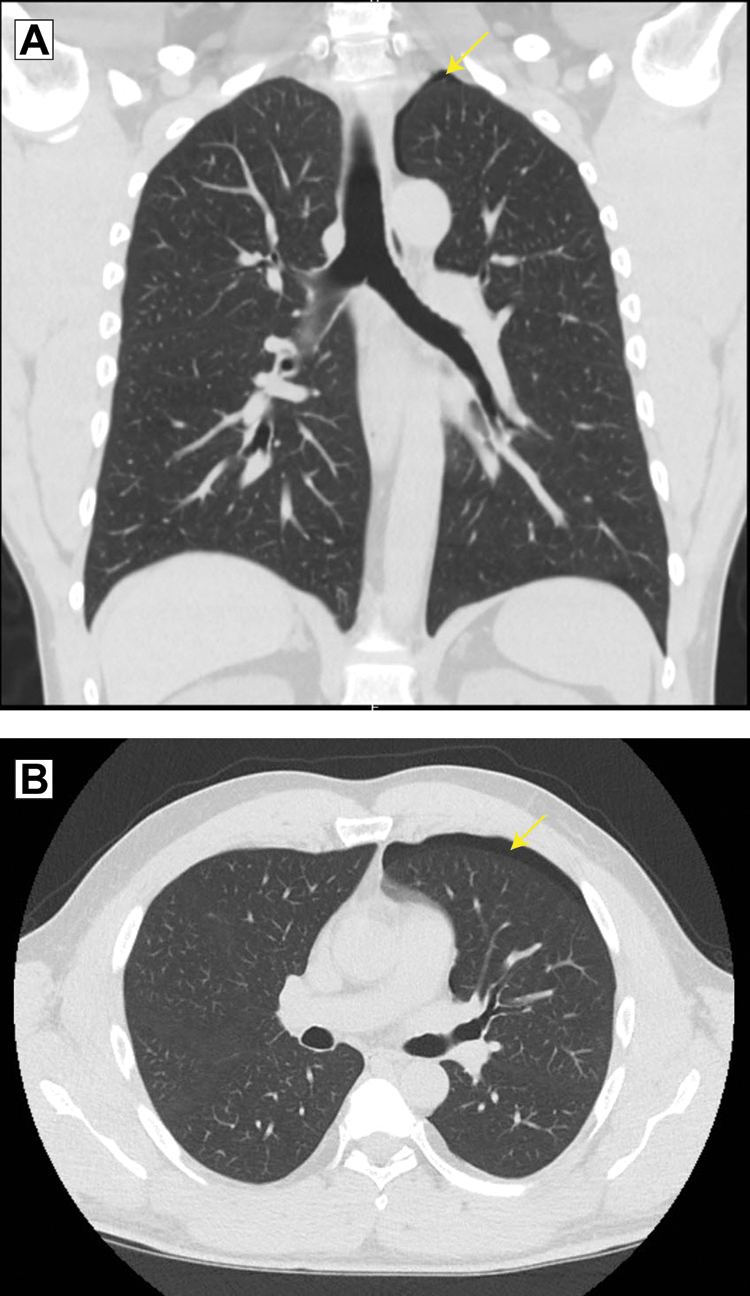

Initial evaluation in the emergency department included complete blood cell count and comprehensive metabolic panel, the results of which were unremarkable. Because of the dry cough, portable chest x-ray imaging was done. The radiograph raised concern for left apical pneumothorax (Figure 1). Subsequently, computed tomographic images of his chest without contrast revealed a small left apical pneumothorax (Figure 2).

Computed tomographic images of the chest in the (A) coronal view and (B) axial view demonstrated a small, left-sided apical pneumothorax. The patient was a 44-year-old man who had undergone dry needling of the infraspinatus, supraspinatus, rhomboid, and paraspinal muscles 1 day earlier.